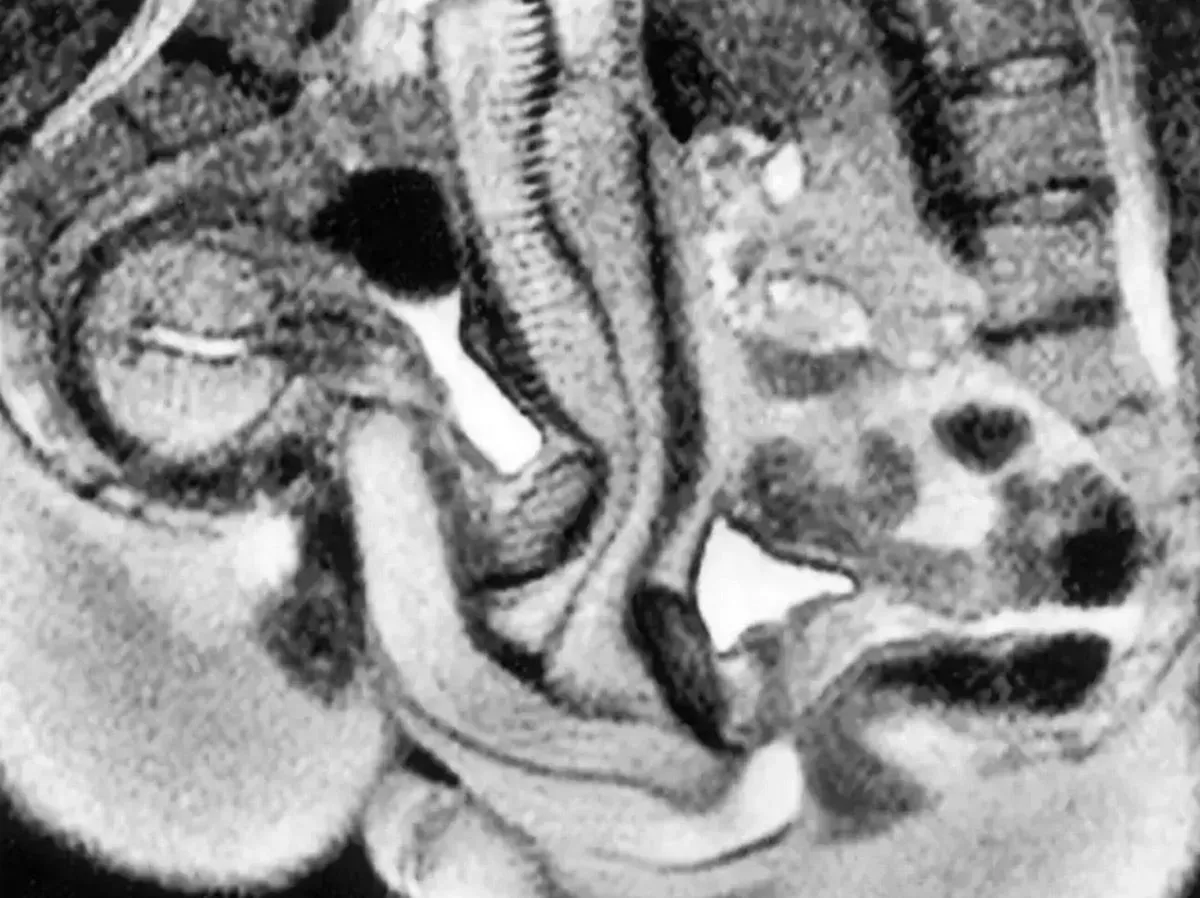

The astonishing study said: “The images obtained showed that during intercourse in the ‘missionary position’ the penis has the shape of a boomerang and 1/3 of its length consists of the root of the penis. During female sexual arousal without intercourse the uterus was raised and the anterior vaginal wall lengthened. The size of the uterus did not increase during sexual arousal.”

The MRI scan gave scientists a real insight into how bodies react during sex(Image: BMJ)